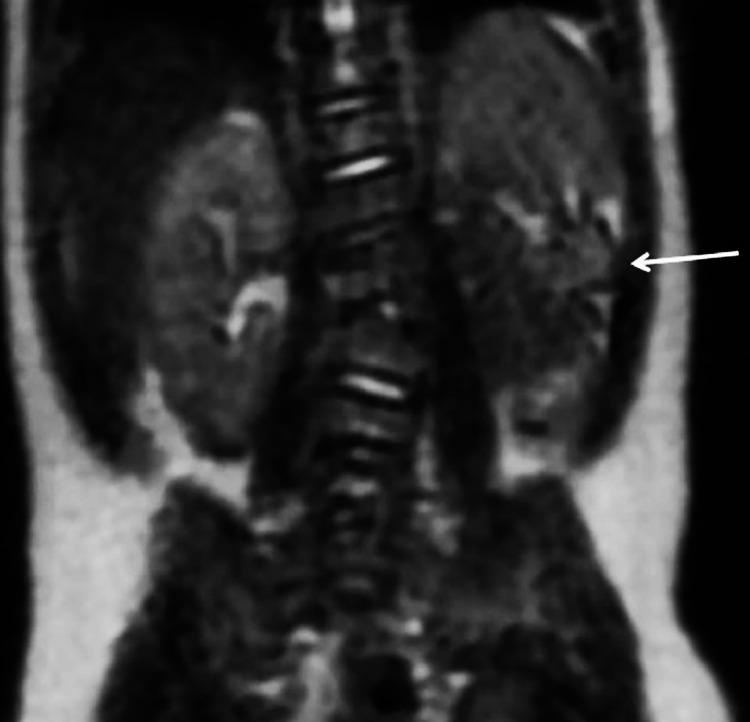

Alagille syndrome is an autosomal dominant and multisystemic disease that generally manifests itself with intrahepatic bile ducts paucity, chronic cholestasis, xanthomas and with other less frequent clinical manifestations such as congenital heart disease, skeletal abnomalies, ophthalmic, vascular, renal and growth failure. Symptoms can be subclinical or very severe. Is caused by various genetic mutations and the majority of patients have a detectable mutation in JAG1 (90%), the remainder have mutations in NOTCH2. The diagnosis is molecular and the incidence is approximately 1 in 30,000 - 50.000. Patient management can be very complex and treatment depends on the district affected and on the symptoms. In more serious cases, with terminal liver disease, liver transplantation is used. We describe a case with main bile duct hypoplasia, intrahepatic bile ducts paucity, cholestasis and gallbladder dimorphism associated with renal malrotation and butterfly vertebrae.

阿拉吉耶综合征是一种常染色体显性多系统疾病,通常表现为肝内胆管稀少、慢性胆汁淤积、黄色瘤,以及其他不太常见的临床表现,如先天性心脏病、骨骼异常、眼科、血管、肾脏和生长发育迟缓。症状可能是亚临床的,也可能非常严重。它由多种基因突变引起,大多数患者在JAG1基因中存在可检测到的突变(90%),其余患者在NOTCH2基因中存在突变。诊断依靠分子检测,发病率约为1/30000 - 1/50000。患者的管理可能非常复杂,治疗取决于受影响的部位和症状。在更严重的终末期肝病病例中,会采用肝移植。我们描述了一例伴有主胆管发育不全、肝内胆管稀少、胆汁淤积和胆囊二态性,并伴有肾脏旋转不良和蝴蝶椎的病例。